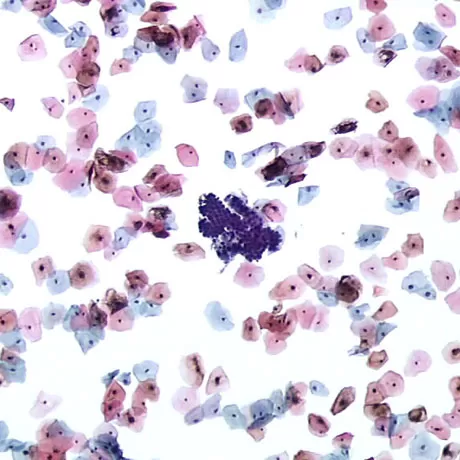

A modern cytological technique recommended by WHO for uterine neck pathology screening

The main distinctions of liquid-based cytology from conventional cytology are:

Our Center employs a fully automated liquid-based cytology system, as well as high-quality stains.